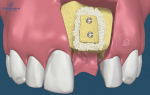

Cấu Tạo Răng Implant Và Các Loại Trụ Implant Phổ Biến Hiện Nay

Phục Hình Răng Sứ Trên Implant